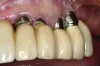

Fig 15. Clinical view of a 65-year-old female patient 5 years after insertion of a porcelain-fused-to-metal prosthesis on six threaded titanium implants in the maxilla (site Nos. 5, 7, 8, 10, 12, and 13). There is no clinically observable recession around the prosthesis or implants.

Accordingly, if an increased rate of bone loss was selected to represent the pace of osseous resorption under dentures, a comparison between the rates of bone loss under dentures and around implants would indicate that implants preserve bone. Furthermore, the preponderance of data document that usually the amount of bone reduction per year around implants, in the absence of peri-implantitis, is so small that it has a negligible effect on the survival of implants, and it would take years to manifest noticeable bone loss and recession. For example, in areas under implant-supported prostheses (Figure 15), the ridge does not routinely manifest bone resorption and recession.66,67 However, there are patients who demonstrate different degrees of bone loss, and the reason for this is unknown.